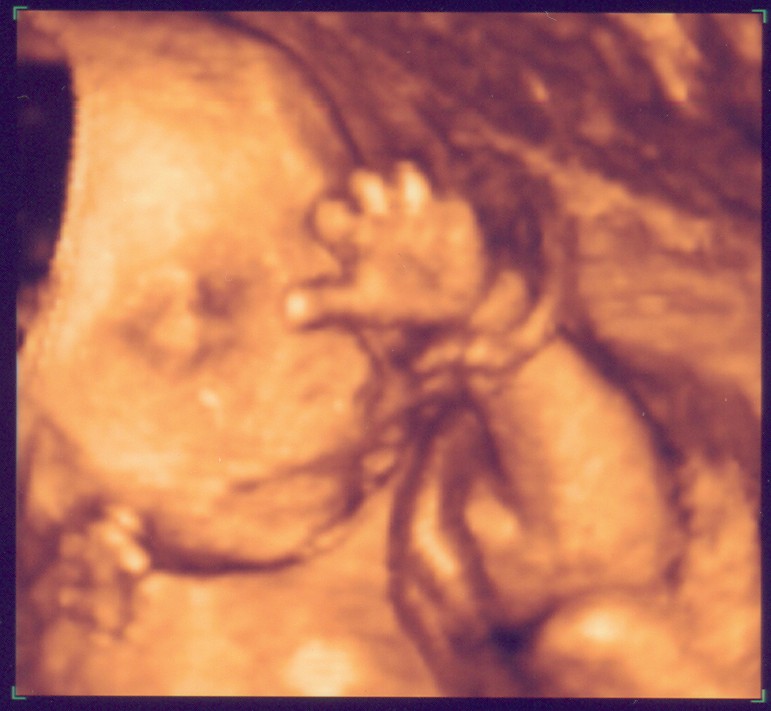

Rechtes Kind im 3D-US

Sorry, dass ich euch bis heute auf die Folter gespannt habe, aber: Nun hat das Warten hat ein Ende ES GIBT NEUE FOTOS!!!

Ist ja echt Wahnsinn, was heute technisch so alles machbar ist. Wir waren übrigens im Klinikum Kassel bei Dr. Simoens. Wenn die Möglichkeit besteht, kann ich das nur empfehlen. Die Wartezeit war extrem kurz und der Doc war sehr nett. Darüber hinaus hat er im Untersuchungszimmer zwei zusätzliche riesige Bildschirme damit sowohl Mann als auch Frau alles sehen können. Echt Klasse.

Hintergrund der Untersuchung war - so die normale Gyn - dass sie bei Mehrlingsschwangerschaften grundsätzlich ein Fehl-/Missbildungs-Sono machen lässt. Soweit es im US ersichtlich war, ist glücklicher Weise alles in Ordnung.

Eure Bilder sind echt toll. Wenn ich mich jetzt nicht allzu blöd anstelle, seht Ihr gleich das aktuellste von unserem Baby. Mit 3-D kann man schon sehr schön alles erkennen, aber wir haben auch ganz schaurige Bildchen. Kommt immer darauf an, wie die Mäuse posieren. :wink: